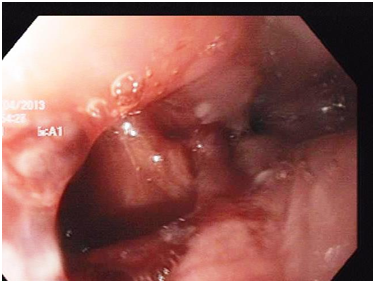

Another upper endoscopy was done and a distal tear was visualized at the distal end (Figure 2), Over-the-scope clip (OTSC) was used to close this tear (Figure 3) (Video). After the closure of the oesophageal, tear with OTSC, CT gastrografin was performed which showed minimal oesophageal leakage (Figure 4).

Figure 3 Upper endoscopic picture showing the use Over-the-scope clip (OTSC) to close oesophageal tear.